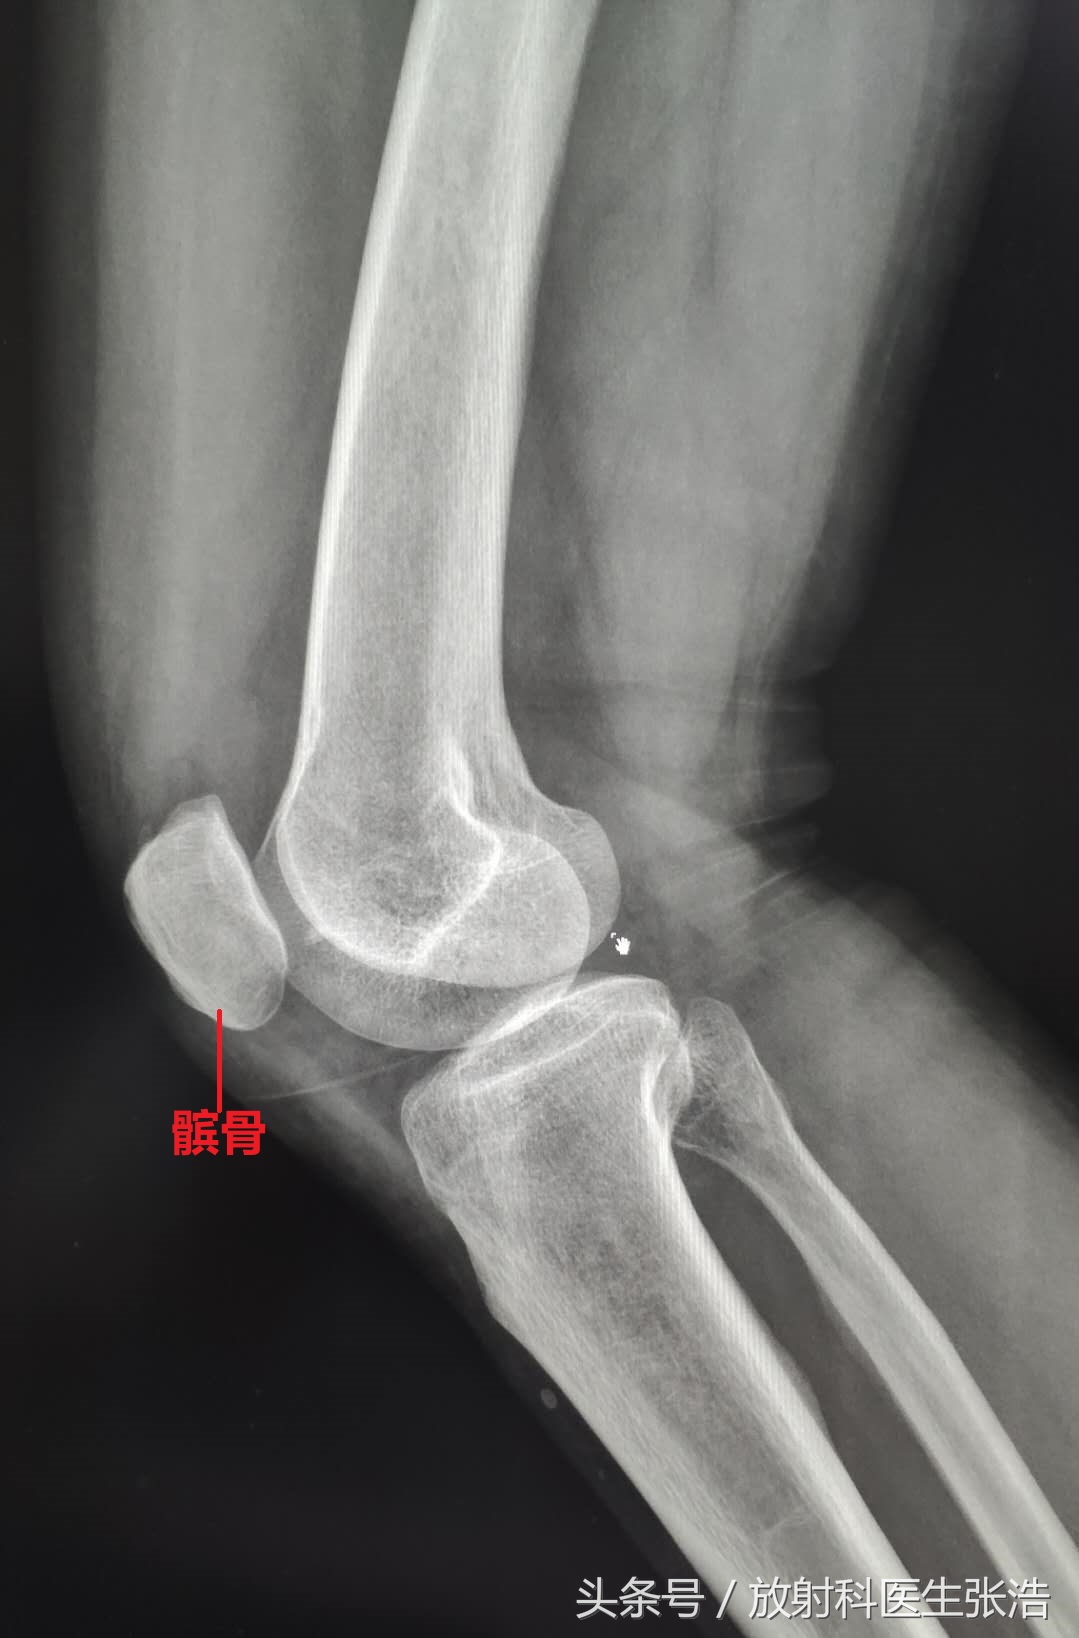

我们通常认为膝关节就是由几块骨头构成的(如上图所示),包括大腿的股骨,小腿的胫腓骨,还有前缘的髌骨,但是实际上膝关节的结构不仅仅有有这些结构,这些我们所熟知的只是膝关节的骨性结构,